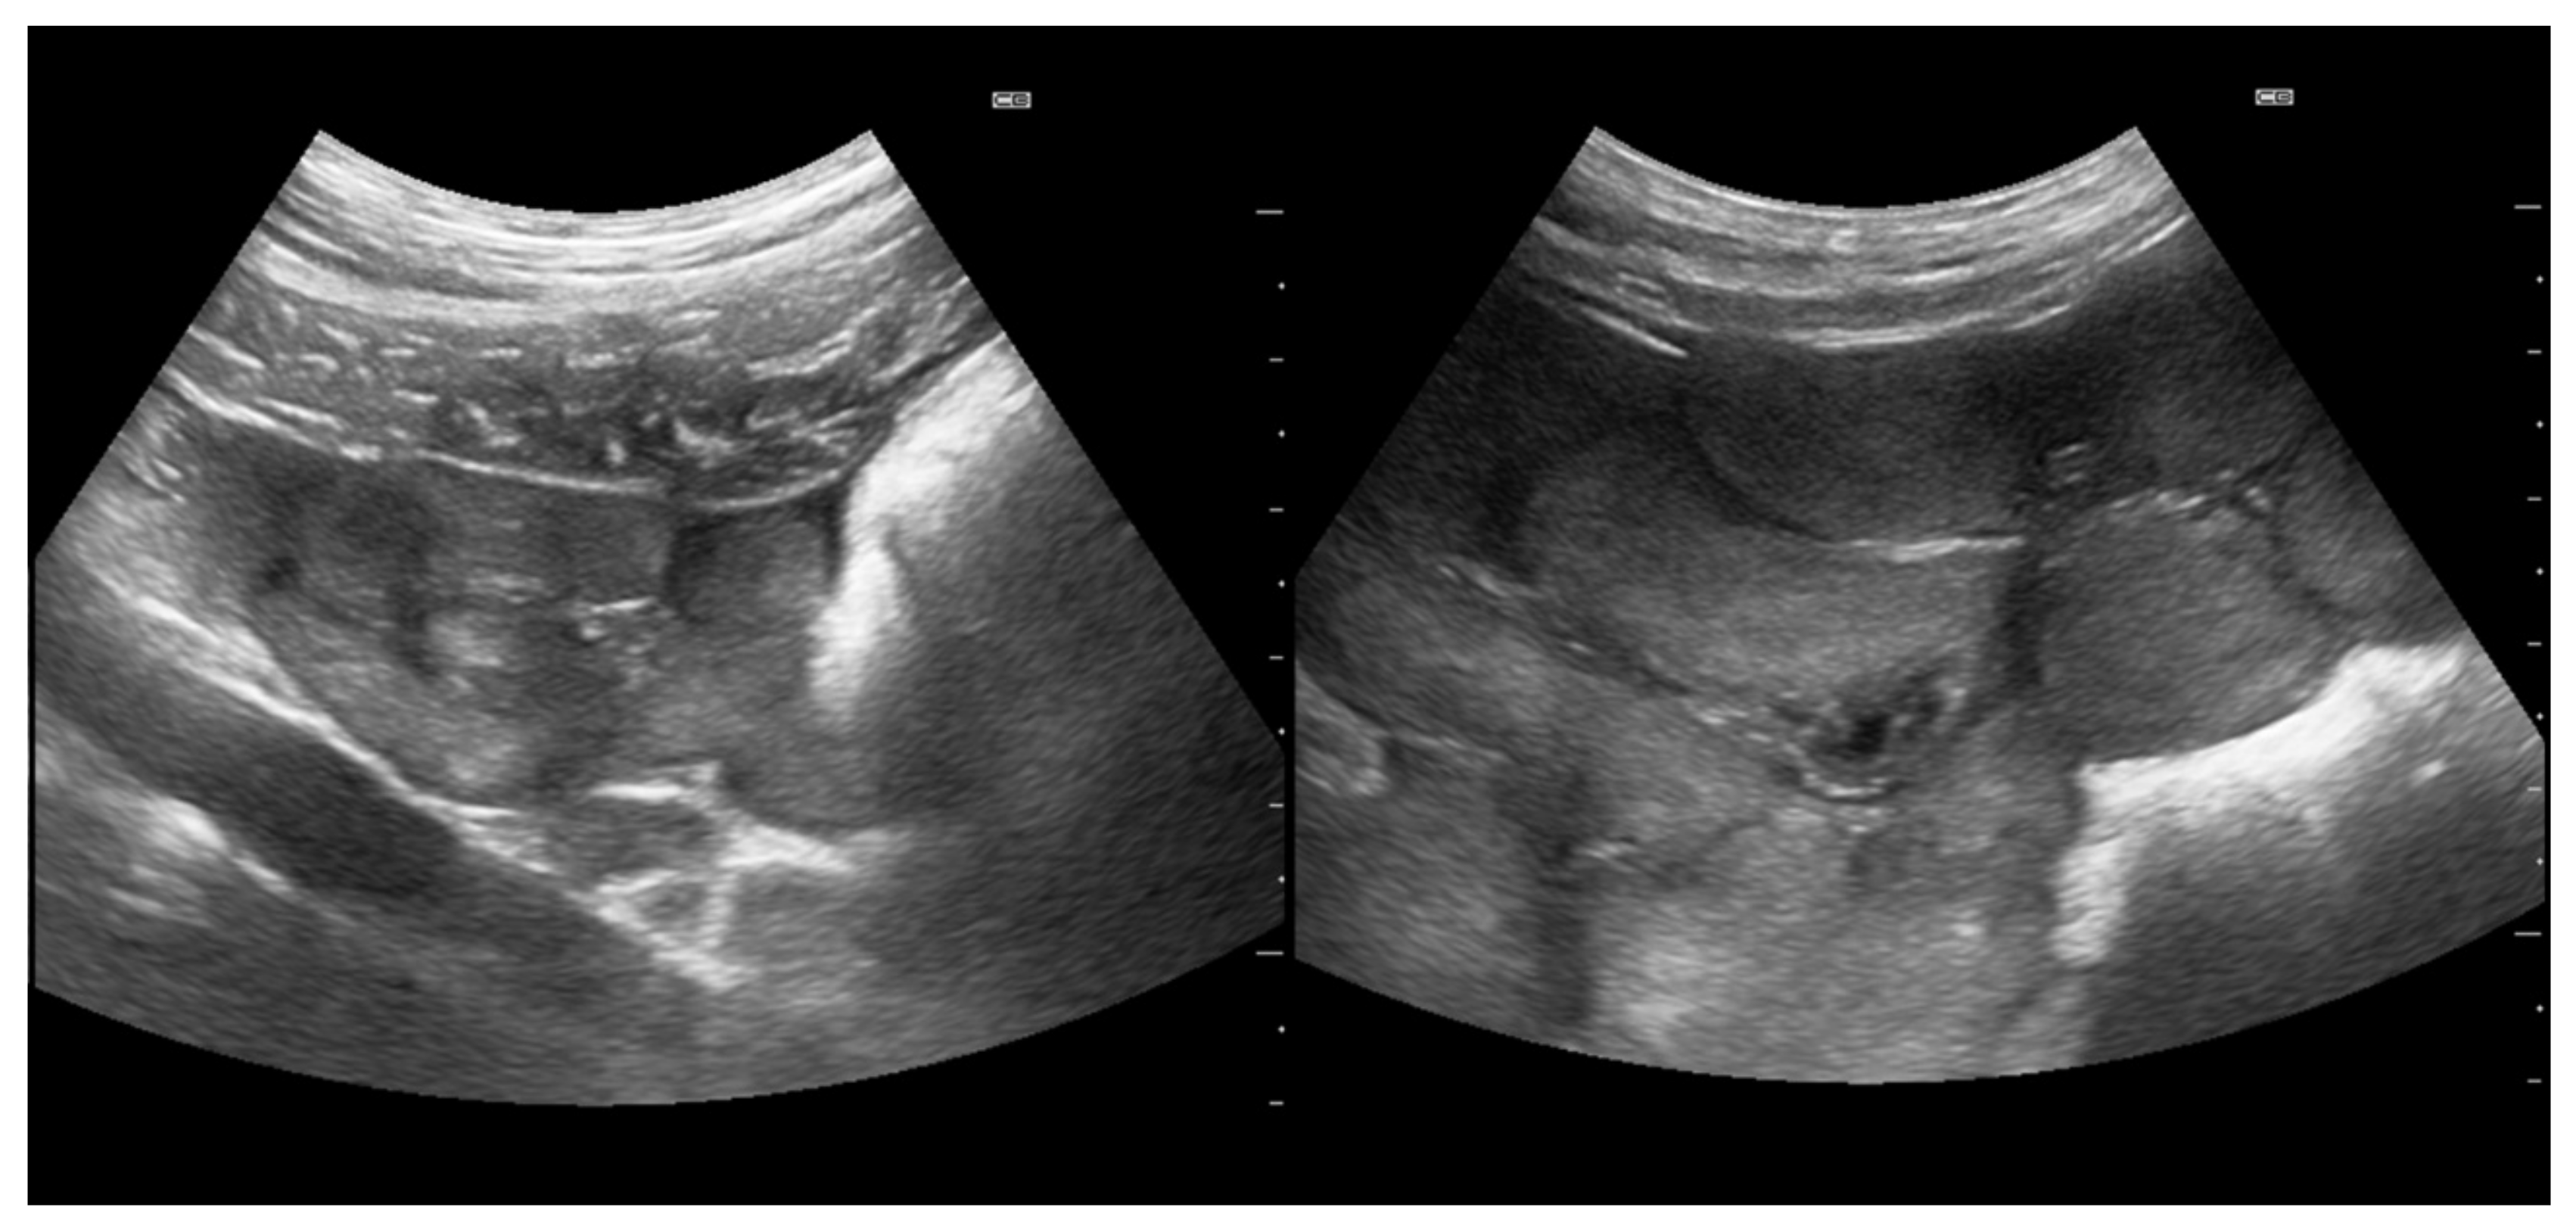

- Kauffold, J.; Rautenberg, T.; Richter, A.; Waehner, M.; Sobiraj, A. Ultrasonographic characterization of the ovaries and the uterus in prepubertal and pubertal gilts. Theriogenology 2004, 61, 1635–1648. [Google Scholar] [CrossRef]

- Vela, A.; Suárez-Usbeck, A.; Lafoz, L.; Mitjana, O.; Tejedor, M.T.; Martín, S.; López, M.; Falceto, M.V. Determination of puberty in gilts: Contrast of diagnostic methods. Porcine Health Manag. 2022, 8, 28. [Google Scholar] [CrossRef] [PubMed]

| Mean cross-sectional area of uterine horns (cm2) | 132 | 1.63 ± 0.48 | 13 | 0.51 ± 0.15 | <0.001 |